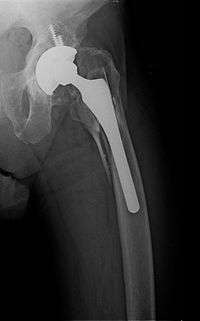

Periprosthetic fracture of left femur

Proximal femur nail with locking and stabilisation screws for treatment of femur fractures of left thigh.